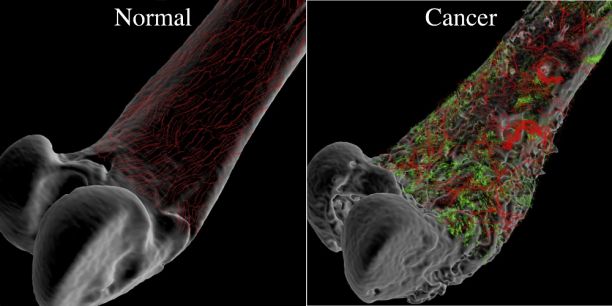

عکس سرطان استخوان. برخی از انواع اصلی سرطان استخوان عبارتند از. سرطان مغز استخوان یکی از انواع سرطان است که به دلیل اختلال در تولید گلبول ها و پلاکت های بدن به وجود می آید. رشد ناهنجار استخوان می تواند بدخیم یا خوش خیم باشد. این تصویر سرطان استخوان است که کاملا روی جمجمه قابل دیدن می باشد.

روش های عکس برداری می توانند به تعیین محل و اندازه ی تومورهای استخوان و گسترش یا عدم گسترش آن ها به سایر نقاط بدن کمک کنند. در این مقاله با علائم سرطان مغز استخوان و نیز روش های درمان آن آشنا می شوید. یک تومور رشد غیر طبیعی بافت در بدن است. سلول های توموری توانایی تنظیم کردن ندارند بنابراین سلول های بیشتری تولید می کنند و منجر به تشکیل یک توده می شوند در حالی که بسیاری از تومورها سرطانی.